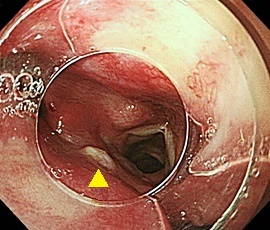

[咽頭腔外魚骨異物] 手術:内視鏡的粘膜下層剥離術(異物除去)

内視鏡画像